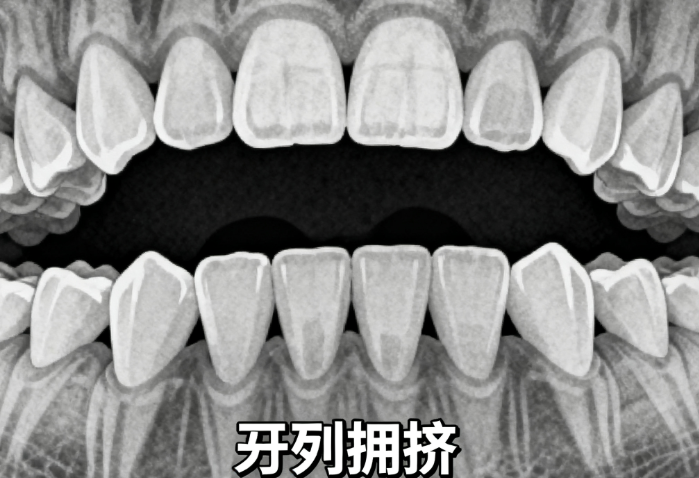

2、矫正难度:简单的牙齿排列不齐,矫正时间短,价格相对低,如轻微拥挤可能3000-10000元;复杂的咬合问题或较重畸形,矫正时间长且方案复杂,价格可达20000-50000元。